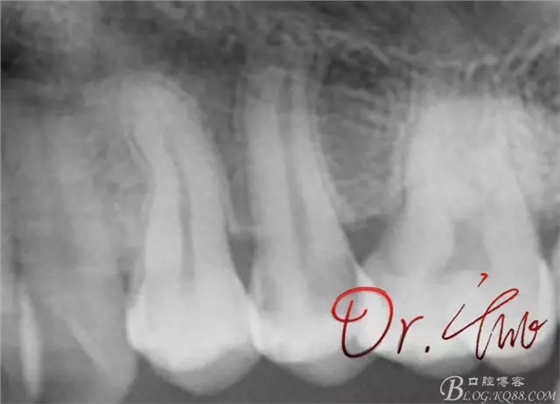

先來第一個病例

初診照